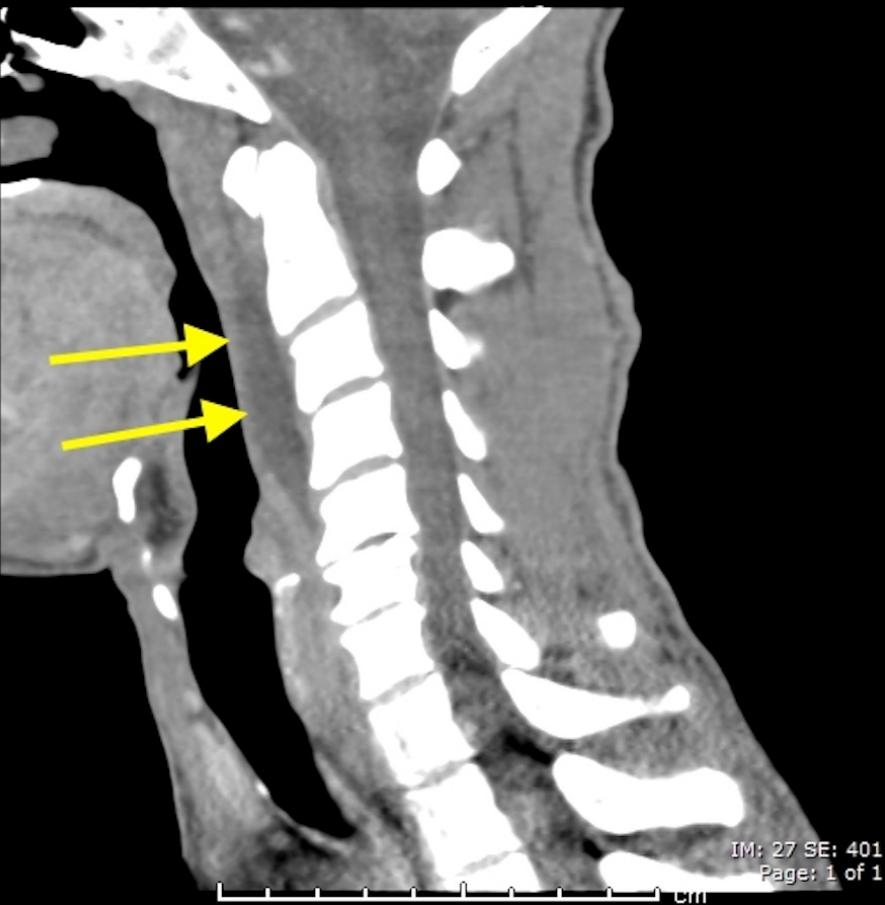

30岁女性,诊断为颈长肌钙化性肌腱炎,但钙化位于不寻常的位置:C4-5椎间隙前侧。A:颈椎侧位片示寰枢椎半脱位(长箭头)和椎前软组织肿胀(无线箭头);B,C和D:颈椎MRI示C1-6椎前软组织肿胀伴积液,D示齿状突骨侵蚀(无线箭头)

上述病人,E为增强,F为抑制像,G和H:经非甾体抗炎药治疗3天后查颈椎CT示C4-5椎前无定形钙化。

上述病人,I和J: 入院4天后复查颈椎MRI示椎前积液明显减少; K,随访2个月复查CT示C4-5前钙化灶减小。(PMID: 21852912)